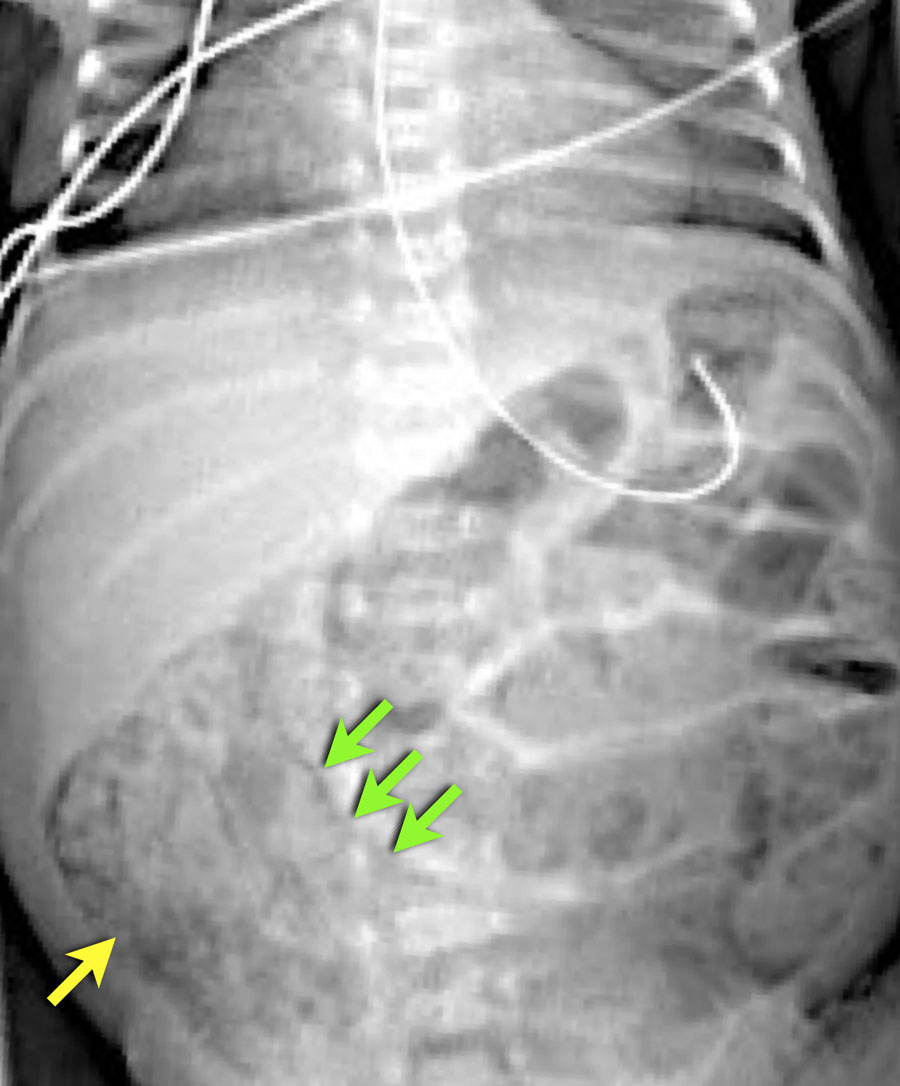

Đây là một trường hợp điển hình khác của viêm ruột hoại tử.

Lưu ý hình ảnh khí trong tĩnh mạch cửa (mũi tên) và các nhánh tĩnh mạch cửa ngoại vi.

Dấu hiệu này được thấy trên X-quang và siêu âm.

Ở bệnh nhân viêm ruột hoại tử này, hãy chú ý các bóng khí trong thành ruột và trong nhu mô gan.